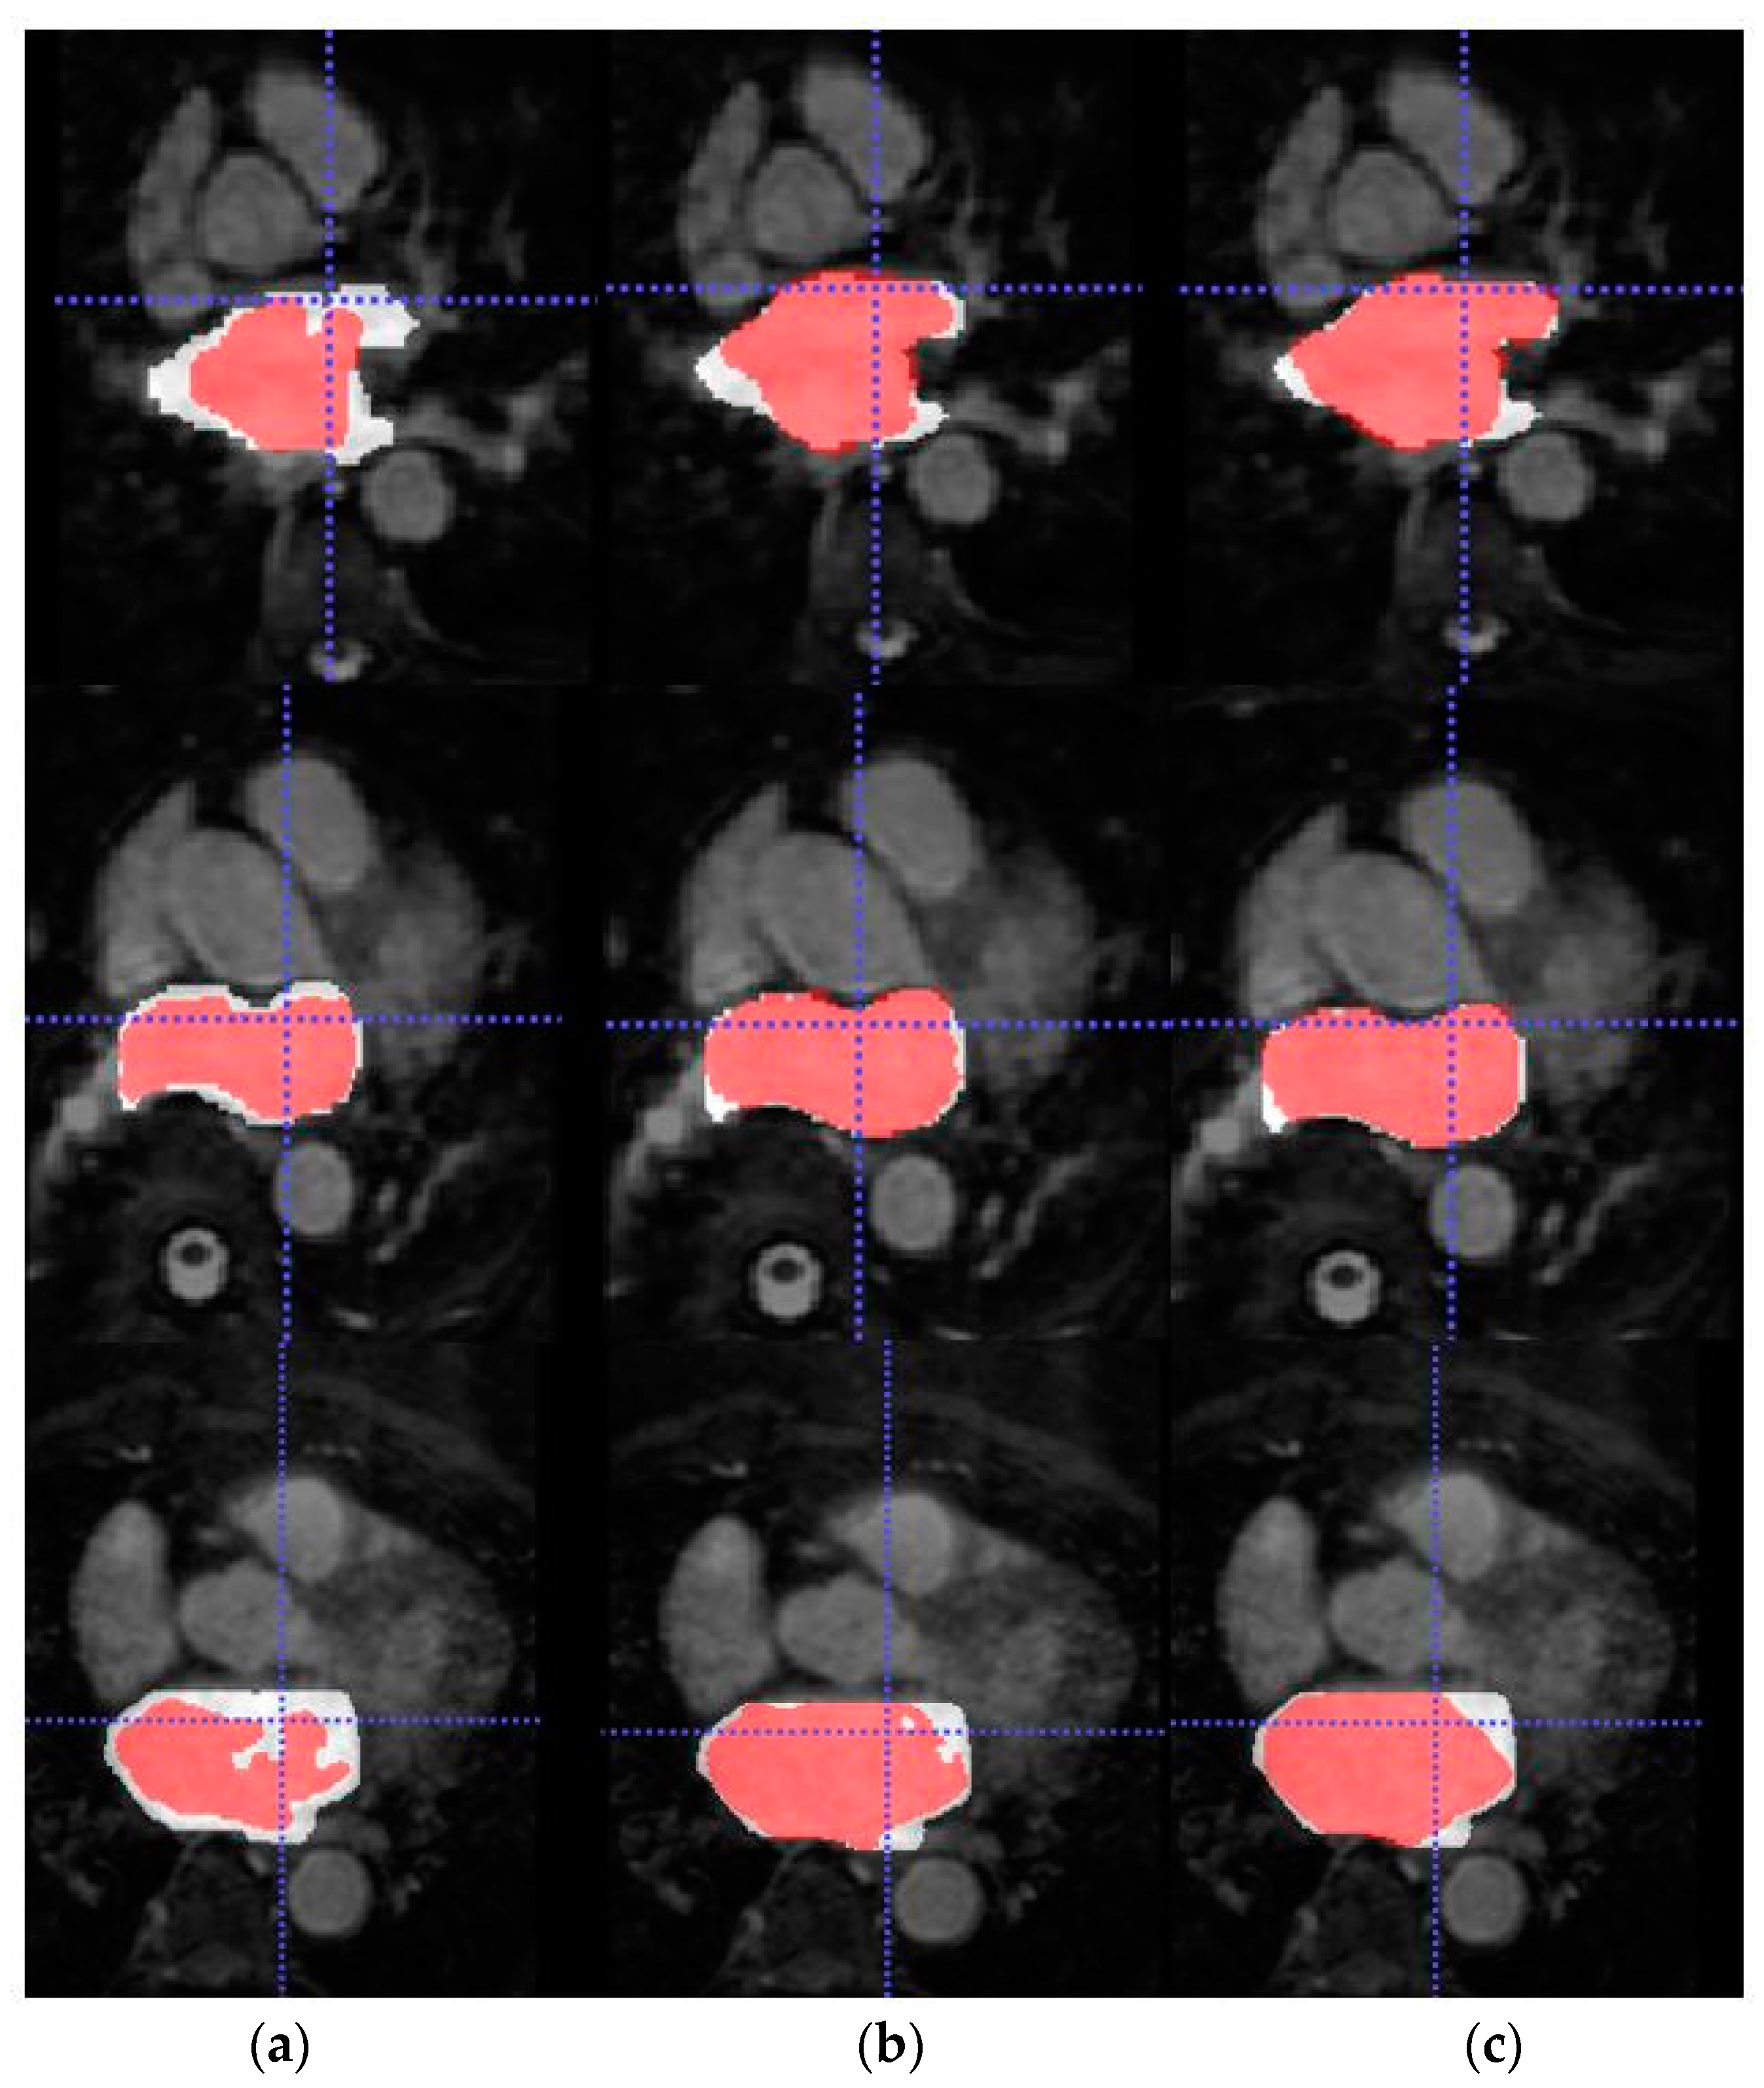

Furthermore, 3D reconstructions of the atrial cavities were obtained from the testing patients of Database 3 to assess the geometry of the predicted segmentations.

Figure 8 shows the 3D reconstruction of both the LA and RA cavities obtained by the trained models bSSFP with and without domain adaptation for two representative patients from Database 3.

In addition, Figure 7 and Figure 8 depict the 3D reconstruction of the prediction segmentation obtained by each trained model. Specifically, Figure 8 shows the increased performance of LA segmentation from the source model to the SDA bSSFP model as the geometry of the cavity becomes more similar in shape to the ground-truth reconstruction. Furthermore, the domain shift problem can be qualitatively assessed as the LGE-MRI source model clearly fails to generate an atrial geometry anatomically similar to the ground-truth. Figure 7 shows the combined reconstruction of LA and RA predictions in bSSFP models with and without SDA. As we can observe with SDA, the overall geometry of the atrial cavities is closer to the ground-truth.

Figure 8. From top to bottom, 3D reconstruction of LA (light gray) and RA (dark gray) segmentations for two representative patients of Database 3 through the models (a) w/o SDA, (b) SDA and (c) ground-truth.